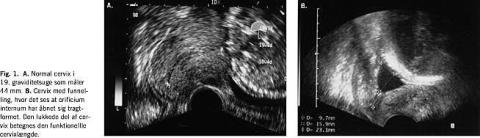

Undersøgelsen foretages med tom blære. Kvinden ligger på et gynækologisk leje eller på et almindeligt leje med en skråpude under sædet. Cervikalkanalen, orificium internum og eksternum identificeres i sagitalt snit, og cervix måles fra orificium internum til orficium eksternum (Fig. 1 ). Der bør observeres i nogle minutter med henblik på at observere eventuelle dynamiske forandringer af cervix. Eventuelt appliceres et tryk på fundus uteri.

Der er lavet flere studier, hvor man har inddraget vurdering af funnelling (tragtdannelse/dilatation af orificium internum) (Fig. 1). Funnelling er dog stort set altid til stede samtidig med en kort cervix, og vurdering af funnelling synes ikke at bidrage yderligere til prædiktionen af spontan præterm fødsel end måling af den funktionelle cervixlængde (den lukkede del af cervix).